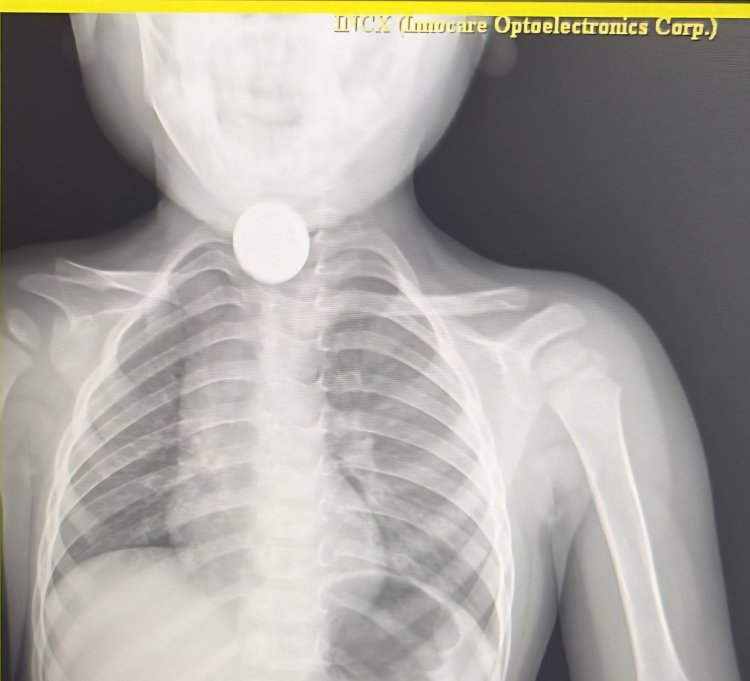

जिला अस्पताल में के डॉक्टर तेजपाल सिंह जादौन ने बच्चों की जांच की उसका एक्सरे कराया जिसमें गले में सिक्का फंसे होने की पुष्टि हुई इसके बाद जादौन ने ऑपरेशन कर दूरबीन की मदद से पांच का सिक्का मुंह से बाहर निकाल दिया सिक्का निकलते ही बच्चे ने राहत की सांस ली परिजनों ने डॉक्टर का आभार व्यक्त किया बच्चों की हालत स्थिर है डॉक्टर ने परिजनों छोटे बच्चों को खेलते समय सावधानी बरतने की सलाह दी